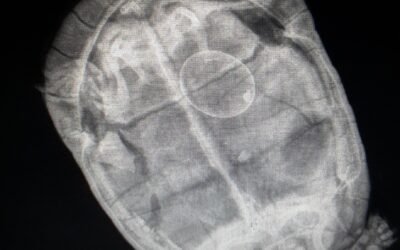

Imagerie médicale

Les examens radiographiques sont effectués au sein de la Clinique Vétérinaire du Mail, ils nécessitent fréquemment une tranquillisation de l’animal afin d’obtenir des images de qualité.Les clichés radiographiques sont remis au propriétaire. Les examens...